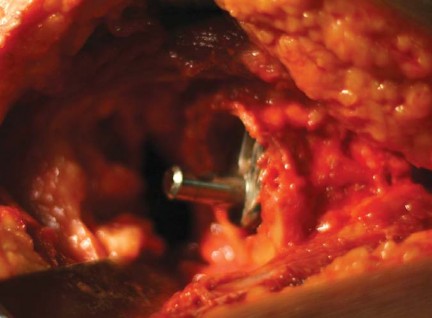

تصميم مفصل METHA

يُعد METHA جذعًا معياريًا، يُثبت في الميتافيزال، وغير إسمنتي. يتميز بتصميم مستوحى من مفصل Mayo الناجح، ولكنه يتفوق عليه في عدة جوانب:

- شكل شبه منحرف واسع: يوفر ثباتًا أوليًا ممتازًا مع الحفاظ على العظم الإسفنجي.

- مادة الصنع والطلاء: يتكون من جذع مخروطي مزدوج من التيتانيوم، مغطى بالكامل بطلاء التيتانيوم النقي المسامي الدقيق (بلازمابور) مع طبقة رقيقة من فوسفات الكالسيوم ثنائي الهيدرات. هذا الطلاء يعزز التوصيل العظمي ويؤدي إلى اندماج عظمي مبكر، مما يوفر ثباتًا ثانويًا.

- الطرف البعيد غير المطلي: يعمل كدليل للزرعة على طول القشرة الظهرية الجانبية، مما يعزز الثبات الأولي العالي. لا يشارك طرف الجذع بشكل كبير في نقل الحمل، بل يعزز الثبات المحوري.

- وحدات الرأس والعنق المعيارية: تتوفر تسعة محولات للعنق مصنوعة من الكوبالت والكروم، بزوايا عنق الفخذ 130، 135، 140 درجة، وزوايا دوران 0، 7.5 درجة أمامية، و7.5 درجة خلفية لكل زاوية. تتوفر الجذوع بسبعة أحجام من 0 إلى 6. تسمح هذه المحولات المعيارية بتحسين ميكانيكا مفصل الفخذ لكل مريض على حدة دون إطالة الطرف.

التقنية الجراحية لزراعة METHA

تتطلب جراحة METHA دقة متناهية وخبرة عالية لضمان أفضل النتائج. يُعد الأستاذ الدكتور محمد هطيف في صنعاء خبيرًا في تطبيق هذه التقنية المتطورة.

النهج الجراحي

يمكن استخدام أي نهج جراحي لزرع METHA. إن قطع عنق الفخذ القريب ونقطة الدخول الإنسية تجعله مناسبًا للنهج الأمامي، الأمامي الجانبي، والخلفي طفيف التوغل. يفضل الأستاذ الدكتور محمد هطيف إجراء الجراحة من خلال شق مناسب الحجم ونهج خلفي، مع وضع المريض في وضعية جانبية.